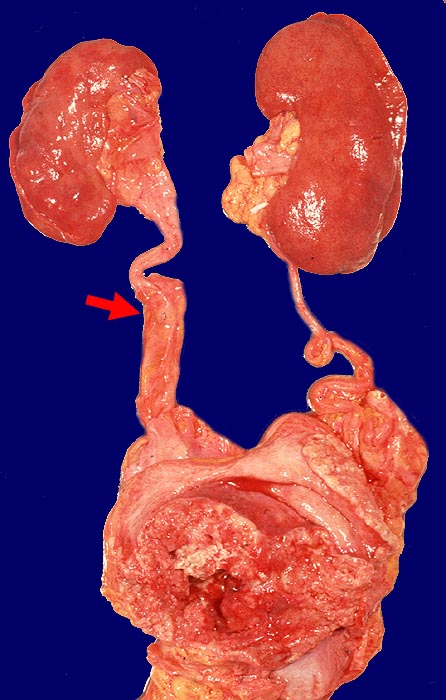

PathoPic ID 954 - Polypöses Harnblasenkarzinom

Polypöses Harnblasenkarzinom

Harnblase

Polypöser Tumor der Harnblase. Tumorstenose des rechten Ureters distal mit geringgradigem

►

Hydroureter rechts.

Wenig differenziertes Urothelkarzinom. Tumordurchmesser 10cm. Infiltration des perivesikalen Fettgewebes mit vesikovaginaler Fistelbildung.

St.n. mehrfacher transurethraler Blasenresektion